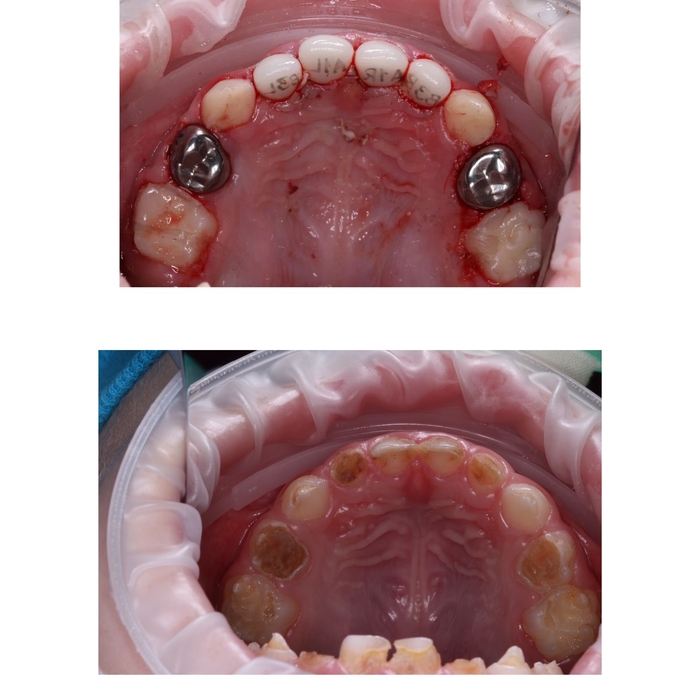

Настал тот день, когда мы пошли к платному стоматологу. Осмотр показал 11 кариесов и 7 пульпитов из 20 существующих зубов. Сделали снимки. Решили попробовать полечить зубы под маской (это когда ребенок через нос вдыхает специальный газ, который расслабляет его. Ребенок в сознании, он смотрит мультики на телеке на потолке кабинета, пока ему лечат зубы). Мой сын в кресло то сел, а вот маску надевать отказался. А если плакать и дышать ртом, она не сработает.

Было принято решение лечить зубы под наркозом (ребенка усыпляют, он спит несколько часов, пока ему лечат сразу все зубы). Был выдан огромный список анализов и консультаций врачей, а еще всякие прививки и справки от педиатра. Мы все собрали, был назначен день наркоза.

В день наркоза мы приехали, поговорили с анастезиологом, потом ребенка завели в операционную и усыпили при нас, а нас попросили выйти.

Муж просидел со мной в палате через стенку от операционной час, а потом уехал на работу. Я осталась. Действие шло 4,5 часа. Сына вынесли, он проснулся и увидел меня. Естественно плакал, жаловался на боль, и я тоже чуть не плакала от его опухшего лица и кровавого рта.

Мы приехали домой, он был вялый, все время лежал, поспал еще 2 часа, вечером поднялась температура. Утром небольшая температура все еще была, поэтому в садик мы его не повели.

Первые 3 дня были самыми тяжелыми, он хотел много всего есть, но не мог из за боли. Сегодня уже неделя с дня лечения, но зубы чистить и мазать десны мазью для заживления получается только через истерику. С едой стало лучше, он пока не ест только конкретно твердые вещи типа яблока.

Итог:

Установлены 4 металлические коронки на жевательных зубах и 4 керамические коронки на верхних передних зубах. Остальное пломбы. Сделала проф.чистка и фторирование, благодаря чему передние нижние зубы стали заметно белее.

Финансы:

- 7тыс за анализы и консультации врачей

- 37тыс за 4,5 часа наркоза

- 103тыс за первичную консультацию стоматолога, снимки всех зубов, консультацию анастезиолога и собственно само лечение и установка коронок

- 3тыс за лекарства для восстановления десен и импортные средства гигиены

Дело происходит в городе-миллионнике.

P. S. Я безмерно рада, что мы наконец это сделали и что кариес не дошел до зачатков коренных зубов. Меня восхищает, что нынешние дети имеют возможность лечить зубы с комфортом и без ударов по психике. Спасибо современным технологиям!